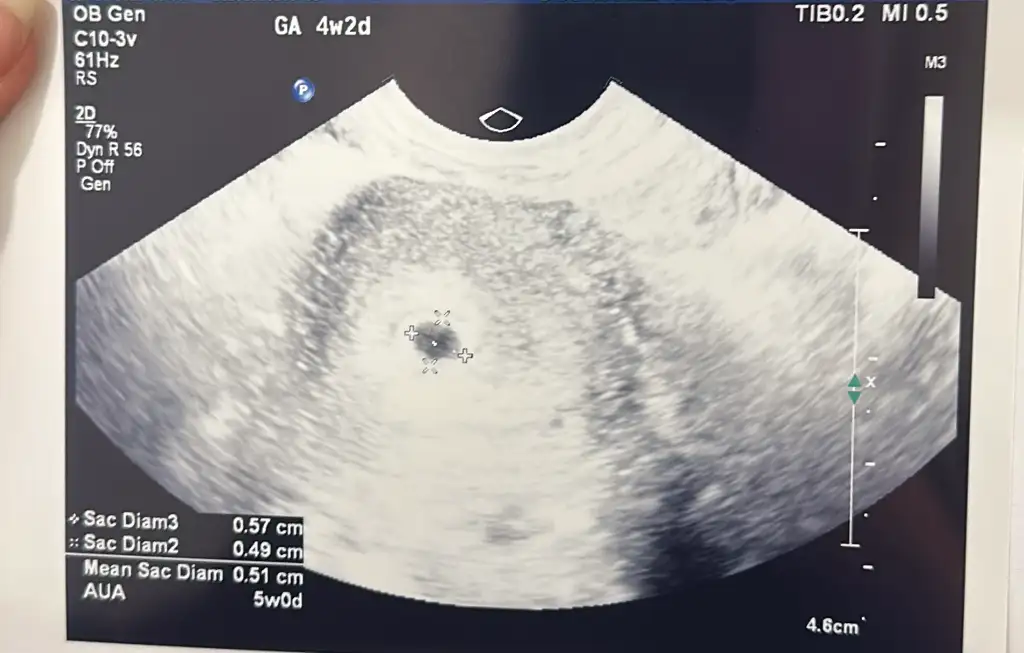

Beta değerim 27 mart 5.6, 29 mart 38.07, 1 nisan 266.79, 4 nisan 1149,6 şeklinde arttı veee bugün keseyii gördüükkk15inde tekrar kontrole gidicem kalp atışını dinleyeceğiz inşallah

5+2 de keseyi gördük. İki tane kese var. Biri diğerinden çok hafif küçük ama anlamlı bir fark değil dedi doktor.Kaçıncı haftada gördünüz keseyi :) tek kese mi var iki kese mi Allah sağlıkla kucağınıza almayı nasip etsin